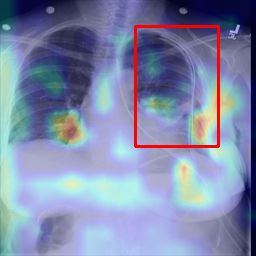

Deployments of artificial intelligence in medical diagnostics mandate not just accuracy and efficacy but also trust, emphasizing the need for explainability in machine decisions. The recent trend in automated medical image diagnostics leans towards the deployment of Transformer-based architectures, credited to their impressive capabilities. Since the self-attention feature of transformers contributes towards identifying crucial regions during the classification process, they enhance the trustability of the methods. However, the complex intricacies of these attention mechanisms may fall short of effectively pinpointing the regions of interest directly influencing AI decisions. Our research endeavors to innovate a unique attention block that underscores the correlation between 'regions' rather than 'pixels'. To address this challenge, we introduce an innovative system grounded in prototype learning, featuring an advanced self-attention mechanism that goes beyond conventional ad-hoc visual explanation techniques by offering comprehensible visual insights. A combined quantitative and qualitative methodological approach was used to demonstrate the effectiveness of the proposed method on the large-scale NIH chest X-ray dataset. Experimental results showed that our proposed method offers a promising direction for explainability, which can lead to the development of more trustable systems, which can facilitate easier and rapid adoption of such technology into routine clinics. The code is available at www.github.com/NUBagcilab/r2r_proto.